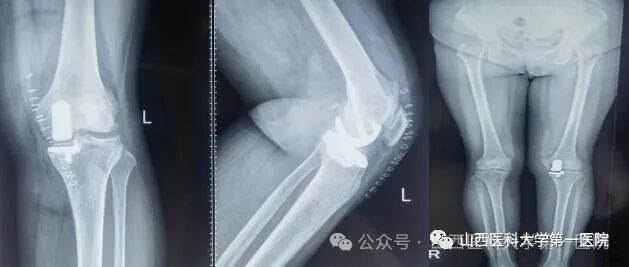

膝关节单髁置换术

同时还在多项技术上实现了零的突破,杨自权主任团队在山西省内开展了首例反式肩关节置换术治疗巨大肩袖损伤,完成了肩关节Latarjet手术(喙突截骨移位术)治疗复发性肩关节脱位以及膝关节单髁关节置换术和复杂髋、膝关节翻修手术等,各类四级手术数量有了较高增长,人工关节置换数量与去年同期相比有了超300%的增幅。